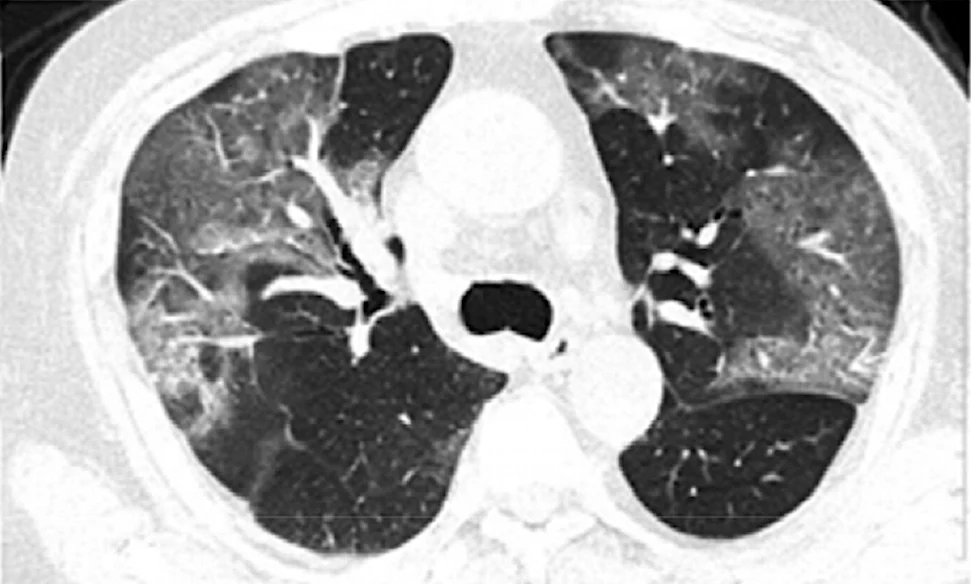

AI in Diagnosis, Telemedicine and Monitoring: AI-Powered COVID-19 Surveillance Solutions

Beyond the AI-Powered COVID-19 Surveillance Solutions, AI also strengthened healthcare systems through:

- AI-assisted CT scan and X-ray interpretation